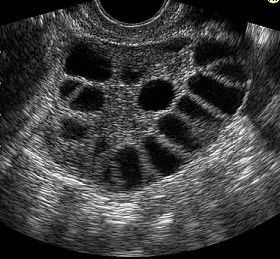

PCOS dramatically impacts the lives of millions of women world wide. Whether it is through increased facial hair, insulin resistance, infertility or any other symptoms associated with the syndrome, the detrimental effects of PCOS are profound. Consistent with the multitude of symptoms, PCOS has a plethora of potential causes. Genetics, environment, hormones and anatomic conditions all contribute to development of the syndrome.